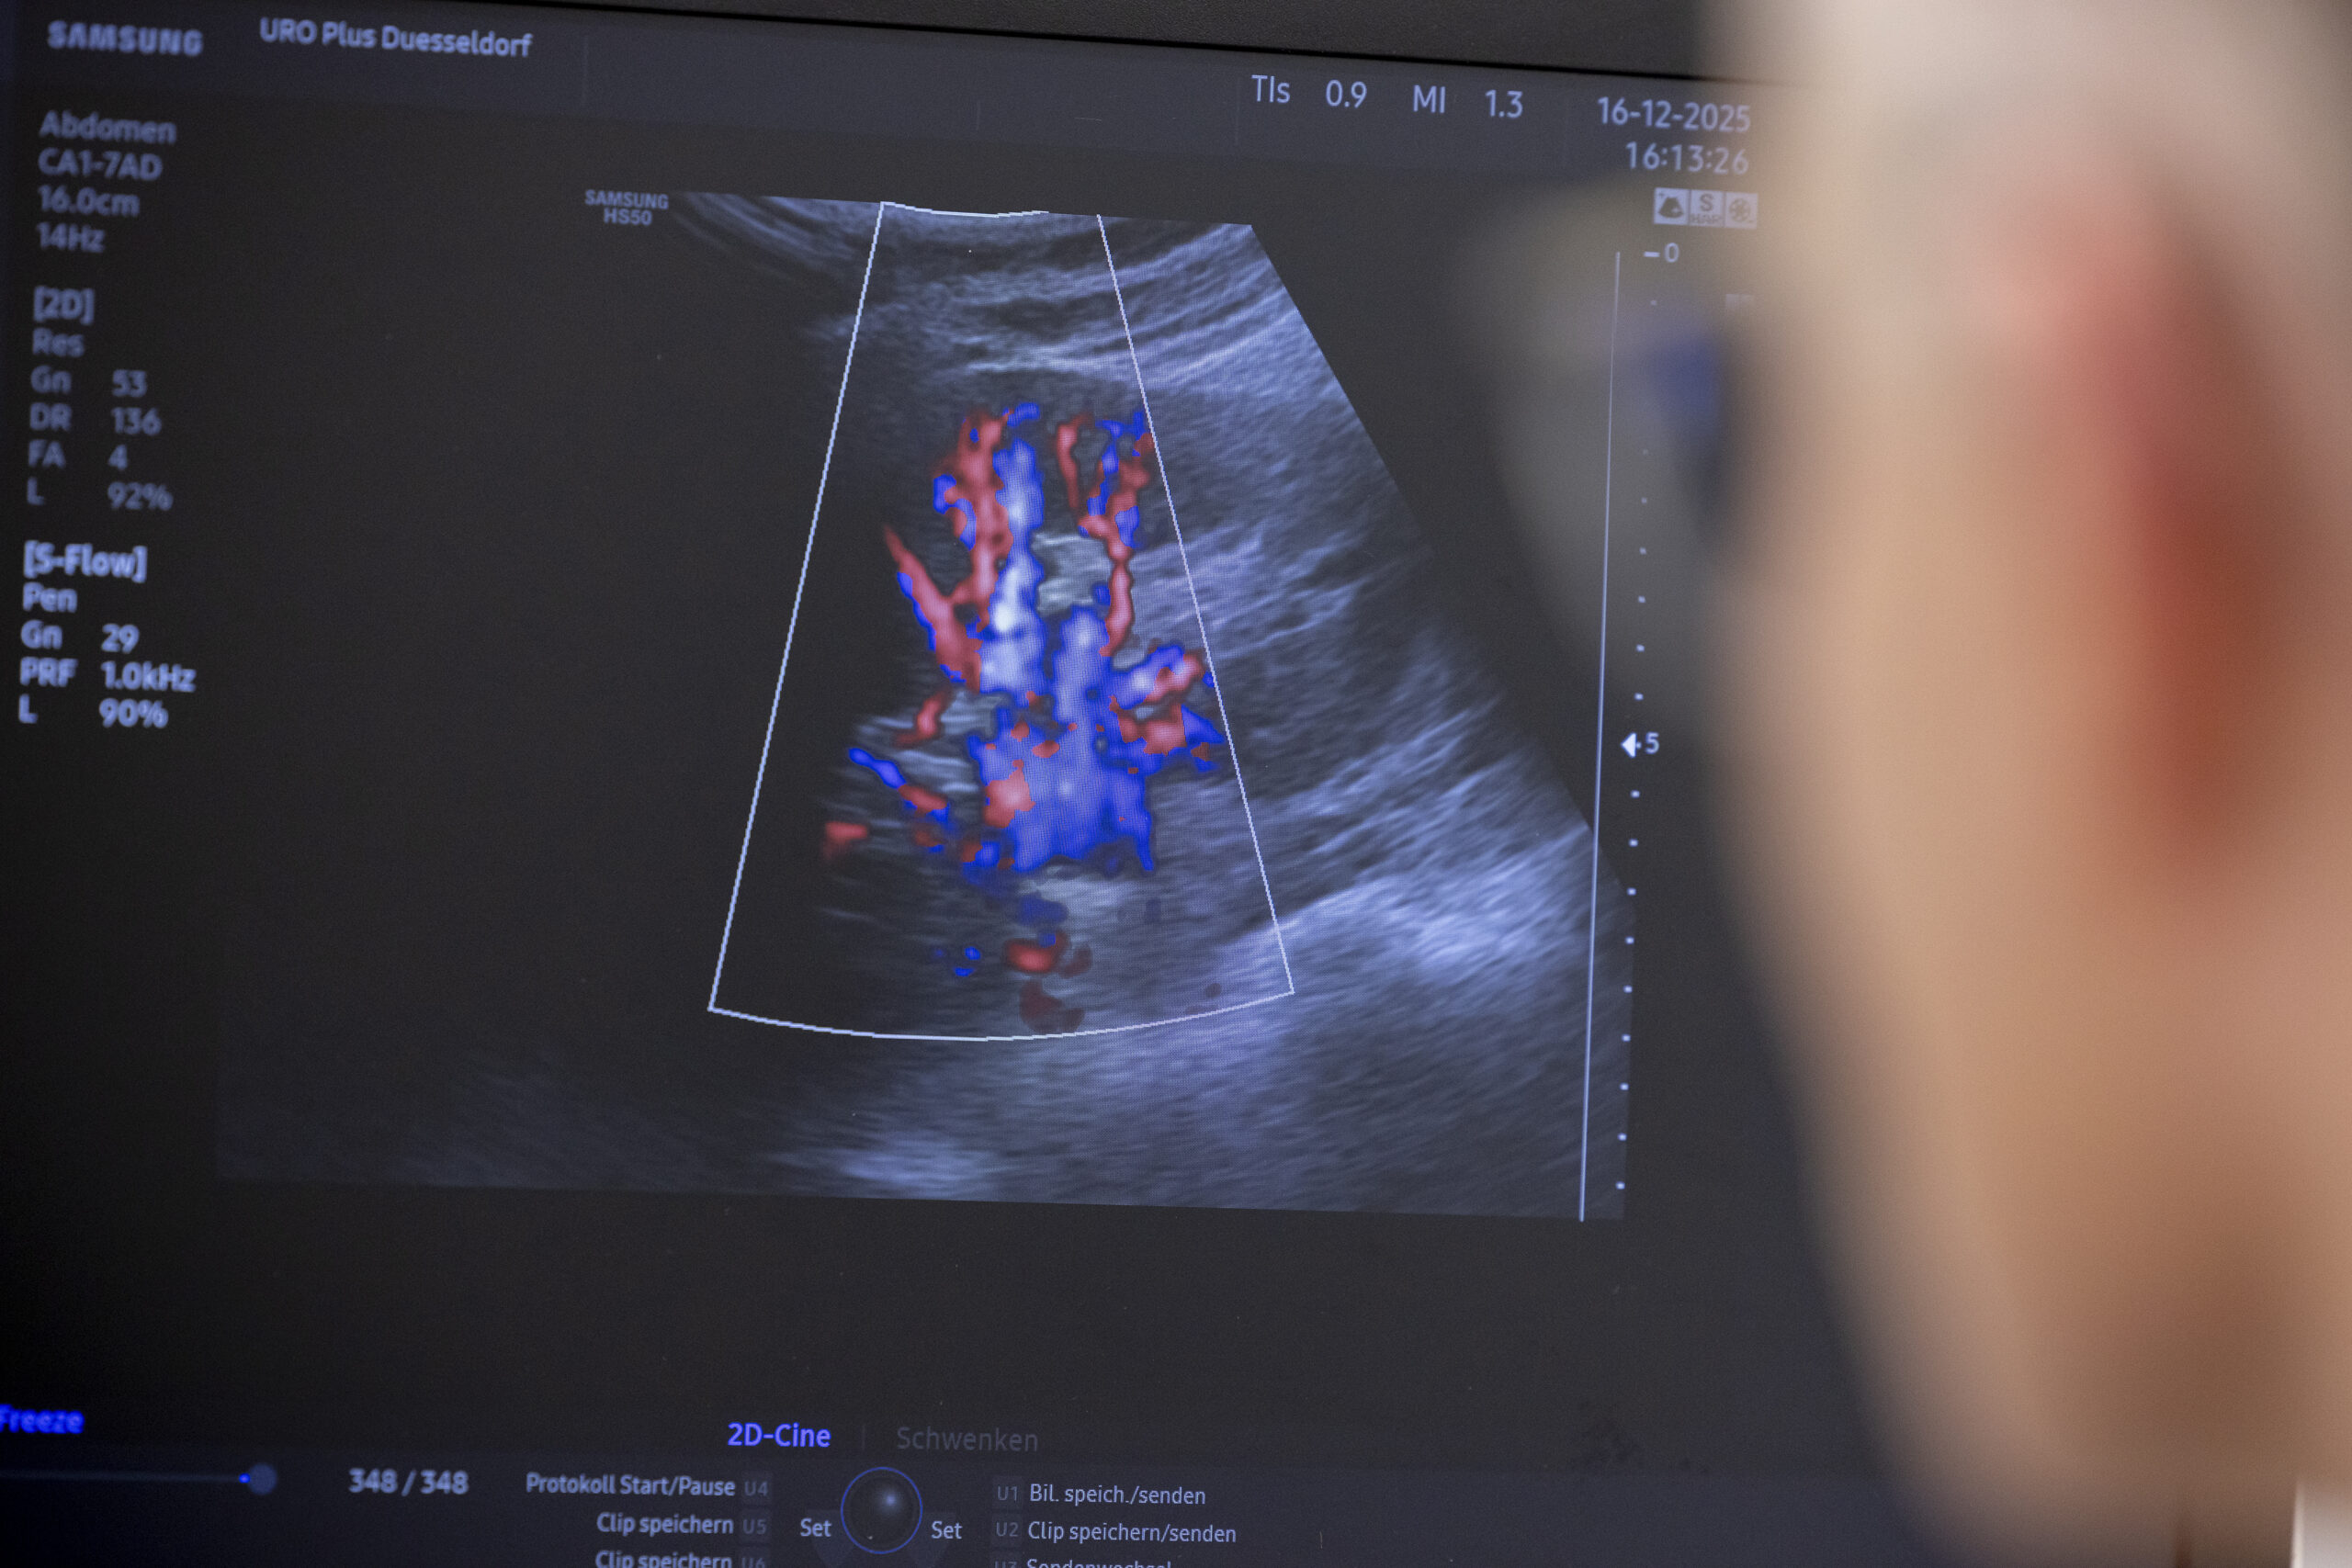

• Bildgebende Verfahren (Ultraschall, MRT, CT) zur frühzeitigen Erkennung von Rückfällen

• Nierenkrebs: Kontrolluntersuchungen mittels Ultraschall, CT oder MRT